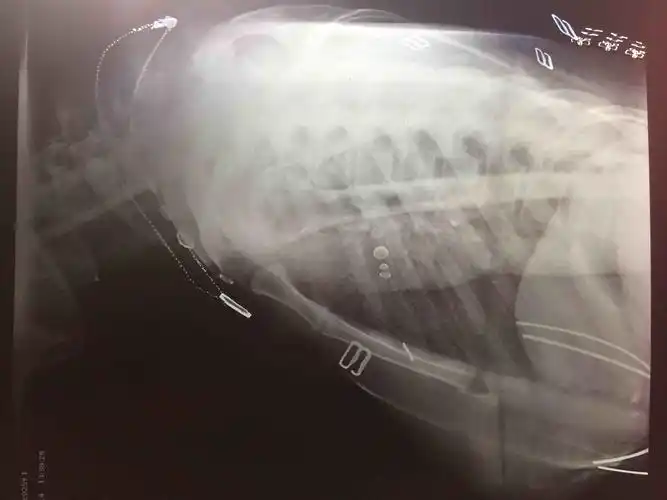

肩关节疼痛肩关节正侧位平片未见明显异常